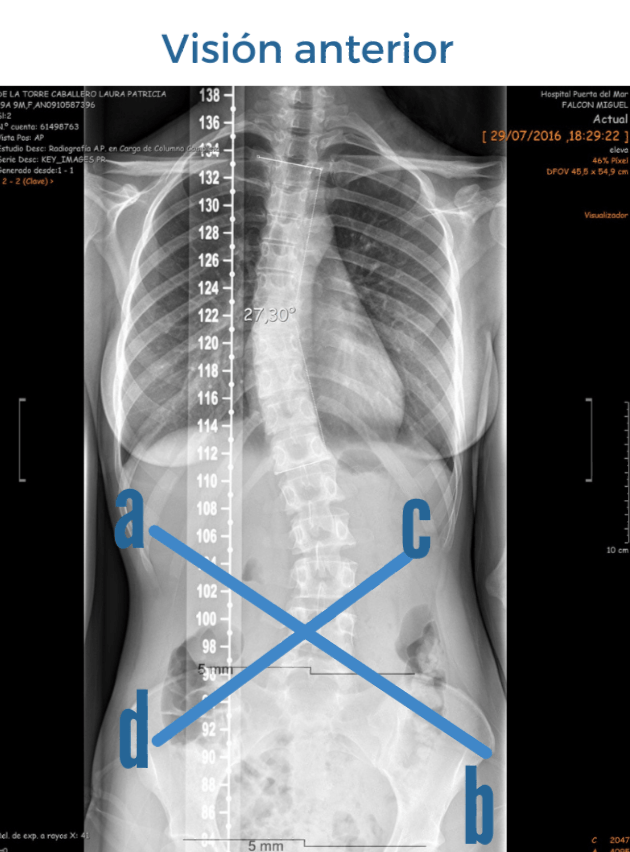

TOMAMOS COMO EJEMPLO UNA ESCOLIOSIS DE CONVEXIDAD DORSAL DERECHA:

Esta rotación a nivel de las últimas costillas (visión anterior) generará un adelantamiento costal bajo izquierdo y la posteriorización del derecho.

Con la pelvis pasará al contrario, la cresta ilíaca del lado izquierdo estará posteriorizada y la del lado derecho anteriorizada.

Esta asimetría se representa con líneas abdominales que van desde la última costilla anterior, hasta la cresta ilíaca contraria.

El músculo oblícuo externo derecho (a) y el oblícuo interno izquierdo (b) se hallan sobreelongados. Y los contrapuestos (c) y (d) se hallan en acortamiento.